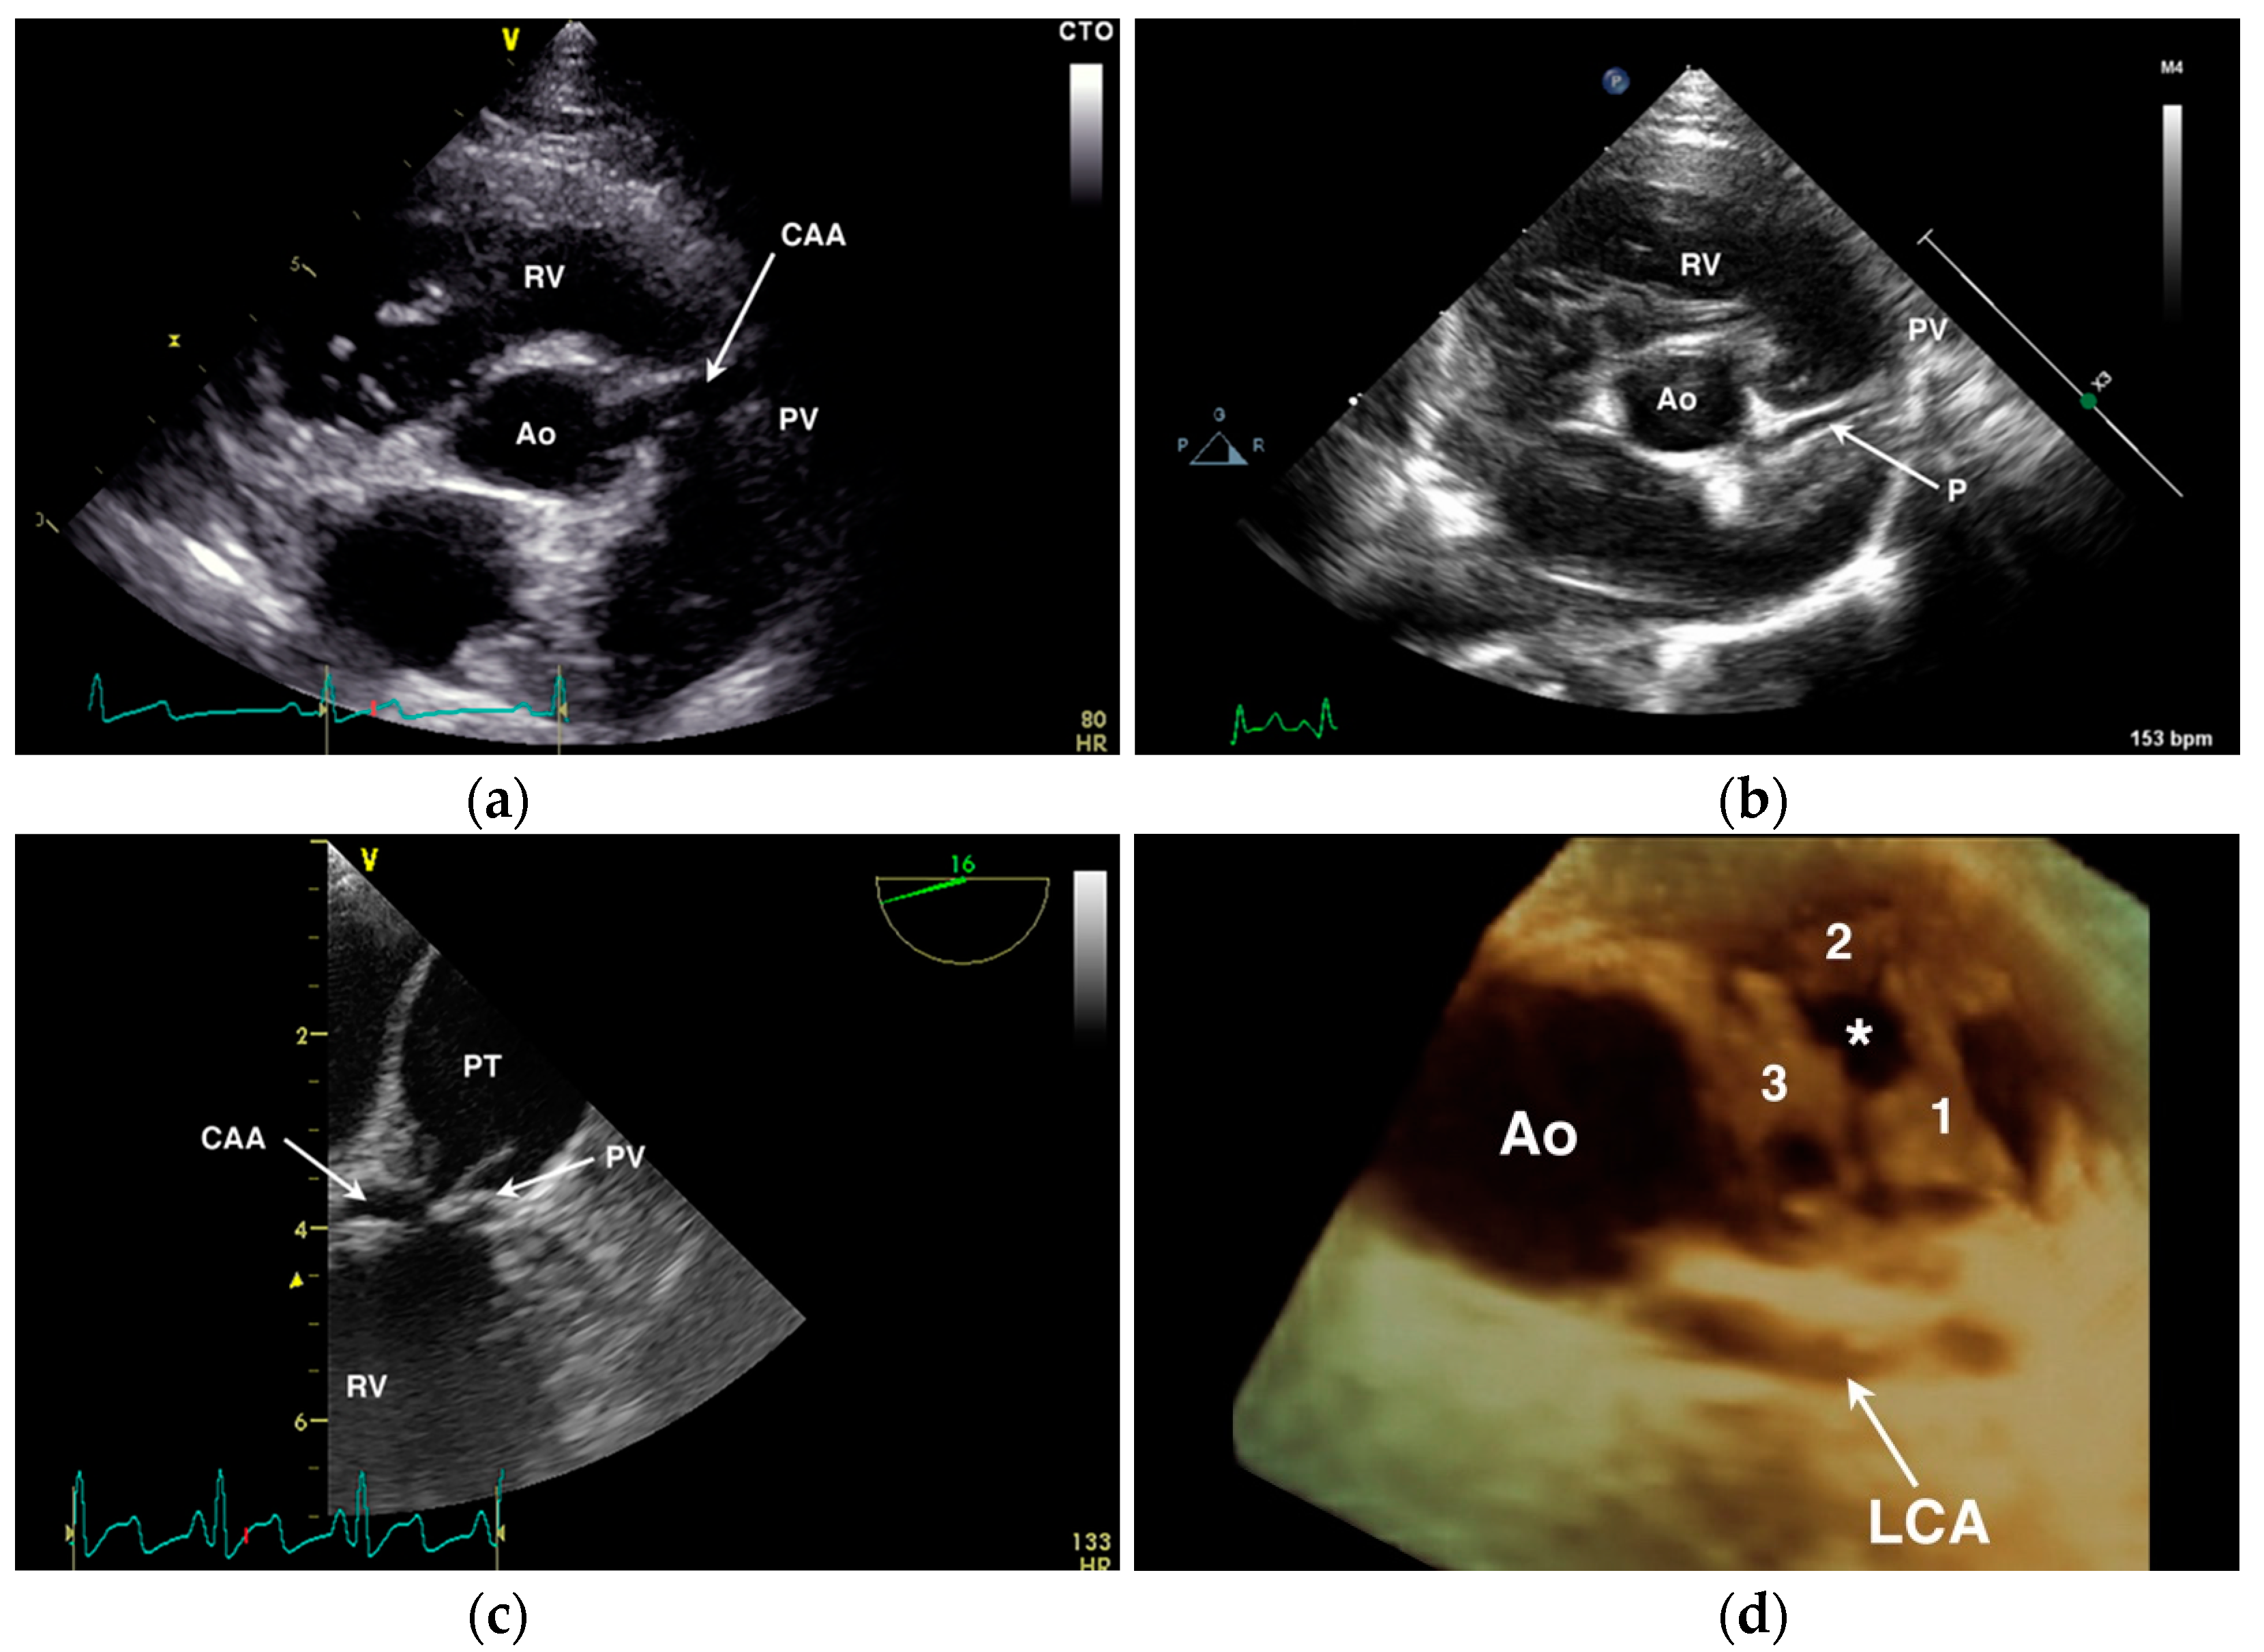

Figure 6.

Echocardiographic examples of anomalous coronary artery origin or course. (a) Transthoracic short-axis image of the aortic root (Ao) showing a large single right coronary ostium with an anomalous coronary artery (CAA) traversing over the pulmonary valve (PV) annulus. RV = right ventricle. (b) Transthoracic short-axis image of the aortic root (Ao) from a dog with normal coronary anatomy demonstrating a normal paraconal interventricular branch (P) that appears to cross cranial to the PV annulus. (c) Transesophageal long-axis image of the RV outflow tract of a dog with a CAA seen crossing the PV at the base of the pulmonary trunk (PT). (d) Three-dimensional transesophageal image of the Ao from a dog with single right coronary ostium and a prepulmonary left coronary artery (LCA) showing the position of the LCA encircling the three PV leaflets (labeled 1 through 3) and the stenotic PV orifice (*).

The appearance of a vessel (parallel double-line echoes) overlying the right ventricular outflow tract on transthoracic echocardiography should be interpreted cautiously. While this finding may suggest a CAA with prepulmonary course (Figure 6A), in the author’s opinion it is not definitive. It is possible to create an image where normal coronary vessels appear to overlie or cross the right ventricular outflow tract—both the accessory branch of the RCA as well as the paraconal interventricular branch of the LCA (Figure 6B) can lie in close proximity to the pulmonary valve and right ventricular outflow tract confusing the diagnosis of a prepulmonary coronary arterial course. With transesophageal echocardiography (Figure 6C), it is possible to more thoroughly interrogate the aortic valvar sinuses for presence/absence of coronary ostia and to follow their proximal course. High take-off ostia or suboptimal imaging planes may still limit conclusive imaging with this modality and determining the course of the coronary vessels beyond their proximal origin can be challenging. Considerable experience is necessary to correctly diagnose coronary anatomy by 2-dimensional echocardiography; 3-dimensional imaging in the author’s experience provides a better overview and a more complete ‘en face’ view of the pulmonary annulus and relationship of a prepulmonary arterial course (Figure 6D). In human medicine, 2-dimensional transesophageal echocardiographic diagnosis of the precise CAA present showed poor agreement with surgical findings and marked differences of interpretation when reviewed by a core laboratory [27]; an evaluation of the potential improvement afforded by 3D transesophageal echocardiographic imaging is not available, to the author’s knowledge. As the therapeutic options and the prognostic significance of correctly identifying a CAA in the setting of PS differ widely from a mistaken diagnosis, the author advises caution in making a definitive diagnosis by 2-dimensional echocardiography and still recommends angiography or cross-sectional imaging in most cases.